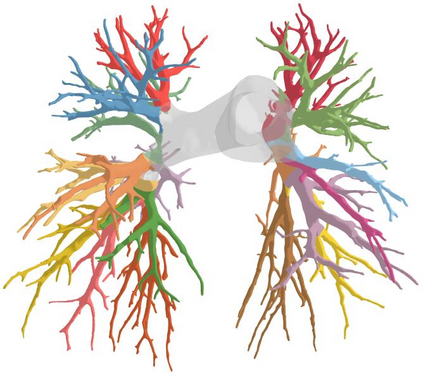

3D reconstruction of pulmonary segments plays an important role in surgical treatment planning of lung cancer, which facilitates preservation of pulmonary function and helps ensure low recurrence rates. However, automatic reconstruction of pulmonary segments remains unexplored in the era of deep learning. In this paper, we investigate what makes for automatic reconstruction of pulmonary segments. First and foremost, we formulate, clinically and geometrically, the anatomical definitions of pulmonary segments, and propose evaluation metrics adhering to these definitions. Second, we propose ImPulSe (Implicit Pulmonary Segment), a deep implicit surface model designed for pulmonary segment reconstruction. The automatic reconstruction of pulmonary segments by ImPulSe is accurate in metrics and visually appealing. Compared with canonical segmentation methods, ImPulSe outputs continuous predictions of arbitrary resolutions with higher training efficiency and fewer parameters. Lastly, we experiment with different network inputs to analyze what matters in the task of pulmonary segment reconstruction. Our code is available at https://github.com/M3DV/ImPulSe.